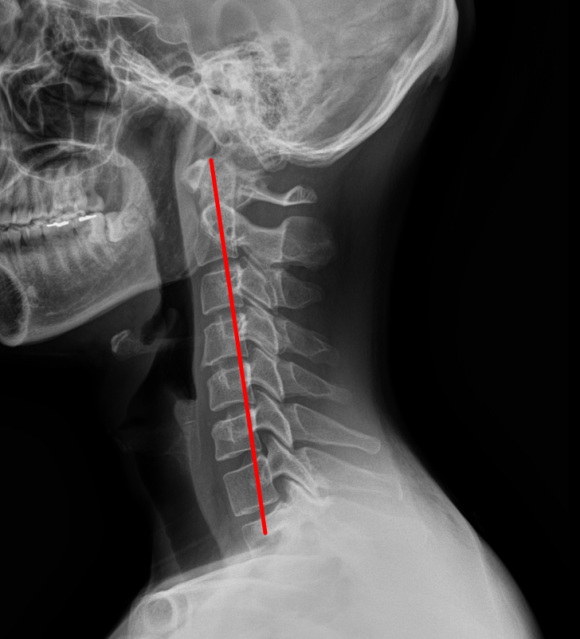

어깨 충돌증후군 & 회전근개파열양쪽 발목 골절 & 인대 완전파열SLAP 파열 & 일자허리일자목 & 디스크 팽륜햄스트링 파열대퇴사두근 파열

경추 X-ray

일자목 & 디스크 팽륜